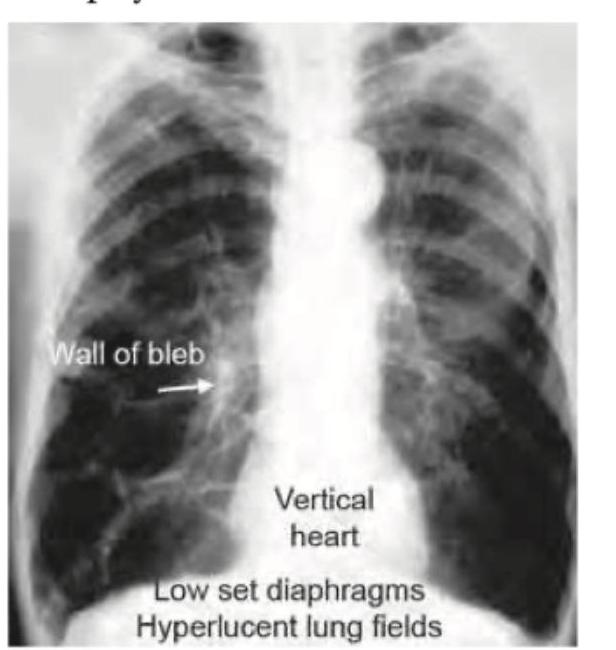

Chronic Obstructive Pulmonary Disease

Practice Questions

Explanation: ***Emphysema*** - **Bullae** are characteristic findings in emphysema, representing abnormally enlarged airspaces within the lung parenchyma. - On CT scans, these appear as demarcated **lucencies (dark areas)**, often with thin walls, indicating destruction of alveolar walls and loss of elastic recoil. *Pneumonia* - Pneumonia typically presents with **consolidation** or **ground-glass opacities** on CT, indicating inflammation and fluid in the alveoli. - It does not typically cause the formation of large bullae; instead, it shows areas of increased density. *Bronchiectasis* - Bronchiectasis is characterized by irreversible **dilation of the bronchi**, often seen as "tram tracks" or "signet ring" signs on CT. - While it can involve air trapping, it does not primarily manifest as large bullae, but rather as thickened and dilated airways. *Interstitial fibrosis* - Interstitial fibrosis involves **thickening and scarring of the lung interstitium**, leading to a restrictive lung disease pattern. - CT findings would typically include **reticular opacities**, honeycombing, and traction bronchiectasis, not bullae.

Explanation: ***Emphysema*** - The CT image displays numerous large, thin-walled **air-filled spaces** or **bullae** within both lung fields, consistent with severe emphysema. - These areas represent the destructive enlargement of airspaces distal to the terminal bronchioles, a hallmark of **emphysema**, often leading to significant loss of lung tissue. - Key feature: **destruction of alveolar walls** with coalescence into larger air spaces without visible walls. *Artifact* - An artifact would typically manifest as streaking, blurring, or other distortions that do not conform to anatomical structures or known pathologies. - The findings here are well-defined, anatomically localized spaces, representing a true pathology rather than an imaging error. *Silicosis* - Silicosis is characterized by **nodular opacities**, interstitial fibrosis, and sometimes mass-like lesions (progressive massive fibrosis), not large emphysematous bullae. - The primary findings in this CT are clearly destructive airspaces, not the fibrotic or nodular changes typical of silicosis. *Bronchiectasis* - Bronchiectasis shows **dilated, thick-walled airways** with a "tram-track" or "signet ring" appearance. - Unlike emphysema, bronchiectasis involves bronchial wall thickening and the cystic spaces are airways, not destroyed alveolar tissue. - The thin-walled bullae in emphysema lack the prominent wall thickening seen in bronchiectasis.